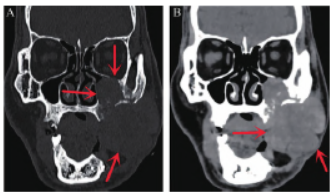

颌面部及颈部磁共振成像

(magnetic resonance imaging,MRI)和CT(图2、3)示:左侧颊癌术后改变,左侧颊部术区新见一大小约5.2 cm×5.1 cm 肿块,考虑颊癌复发。

图3 CT 颌面部平扫增强三维成像。A. 冠状位CT 骨窗示患者术区新发肿块大小约5.2 cm×5.1 cm,向上累及上颌窦壁并突入上颌窦窦腔内,与邻近上颌骨及上牙槽分界不清,部分眶壁受累(红色箭头所指);B. 冠状位CT 软组织窗示患者术区新发肿块向内与舌体分界不清,向外与左侧咬肌分界不清,侵及皮肤(红色箭头所指)。